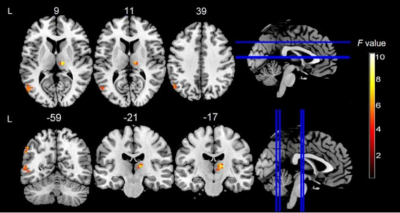

A whole-brain, repeated measures ANOVA (P< 0.001 at the voxel level and P < 0.05 at the cluster level,GRF corrected) revealed that the main influence of time effect on fALFF in the left middle temporal gyrus, right thalamus, and left superior parietal lobule and Reho in left middle temporal gyrus, bilateral thalamus, right rolandic operculum, left cerebellum. Post-hoc two-tailed dependent t-tests with Fisher least significant difference test (Fisher LSD) correction (P < 0.05) based on fALFF averages in the right thalamus and Reho averages in the bilateral thalamus showed that fALFF/Reho significant increase at both 01:00 and 05:00h compared to 9:00, 13:00, 17:00 and 21:00h. A repeated measures ANOVA showed a significant effect of time effect on the 10th and 90th percentiles of RT (F=6.9, P=0.001; F=3.23, P=0.035). At both the 10th and 90th percentiles of RTs, participants had the worst vigilance levels at 01:00 and 05:00h compared to 9:00, 13:00, 17:00, and 21:00h. Decreased vigilance levels coincided with increased rs-fMRI BOLD signals in the thalamus at 01:00 and 05:00h. The present study shows a positive linear relationship between fALFF/Reho in the thalamus and 10th percentile RTs at the same time of day. This relationship between vigilance levels and resting-state BOLD signals may point to a compensatory mechanism for maintaining relative vigilance level.

Significant effect of time effect(9:00,13:00,17:00,21:00,1:00,5:00) for resting-state BOLD fALFF(transverse and coronal).

Significant effect of time effect(9:00,13:00,17:00,21:00,1:00,5:00) for resting-state ReHo(transverse and coronal).